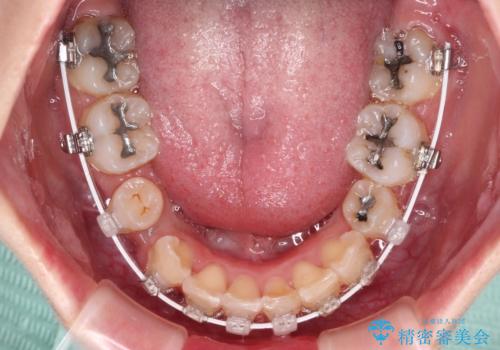

- 矯正装置

- 審美装置

咬み合わせが深く、そのままでは上顎の抜歯スペースが閉じきらない可能性があったため、治療初期から深い咬み合わせを改善させるように試みました。

実際にはなかなか改善されず、当初予定よりも治療期間がやや長期化してしまいました。